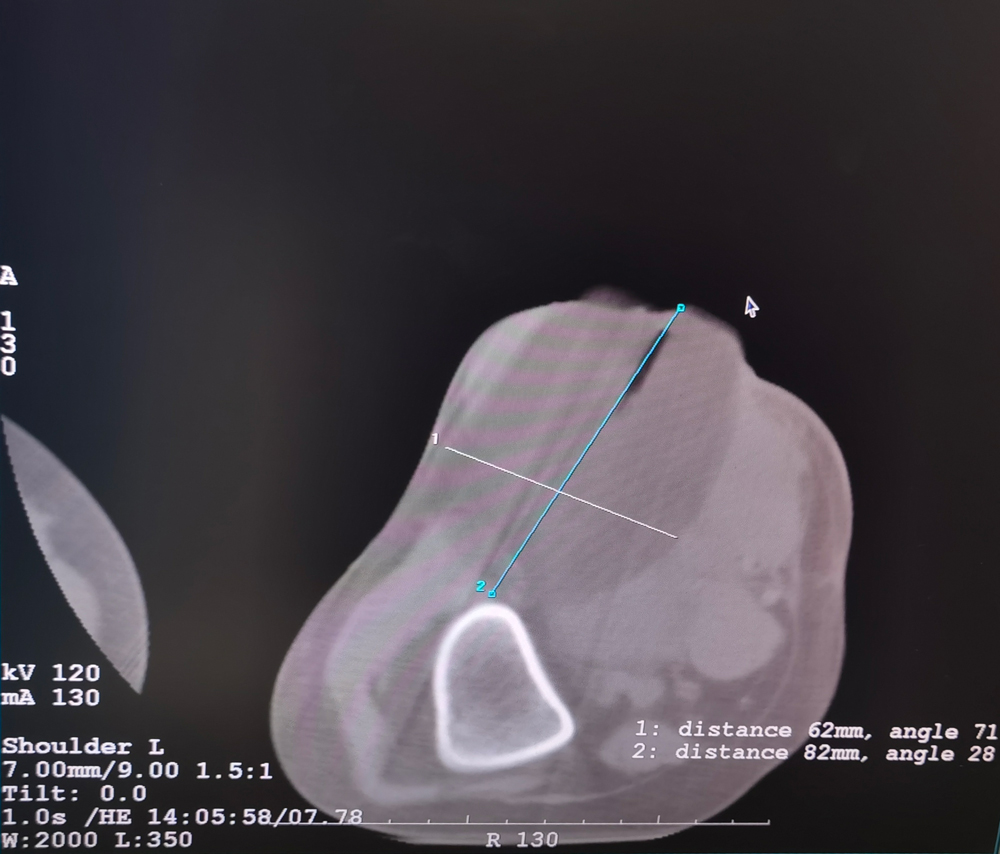

女,42岁,复发性脂肪瘤,病灶位于右侧膝关节,直径大小13cm。采用双针方案,共进行6个冻融循环,最大冰球直径达8.2cm,术中多方位治疗全面覆盖病灶范围。患者术后状况良好。